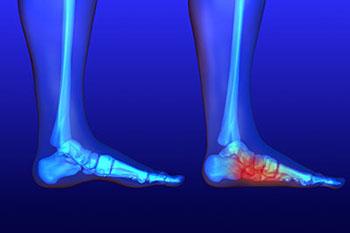

Flat feet is a condition that affects those who have little to no arch in their feet. When you stand, a person who doesn’t have flat feet will have a gap from the inner part of their feet to the floor, due to the normal arch that slightly rises off the ground. Those with flat feet will experience no such gap. While there are some people who experience no issues with their flat feet, it’s not uncommon for those with this condition to experience discomfort or pain.

Flat feet may cause a certain level of pain due to strained muscles and connecting ligaments. Those not afflicted by flat feet are able to get support while walking by the spring that the arch provides, which in turn, helps to distribute your body weight while taking steps. When the arch is no longer present, there is a larger amount of pressure on your muscles and ligaments in the feet, which is why they become strained and may cause you to feel pain.